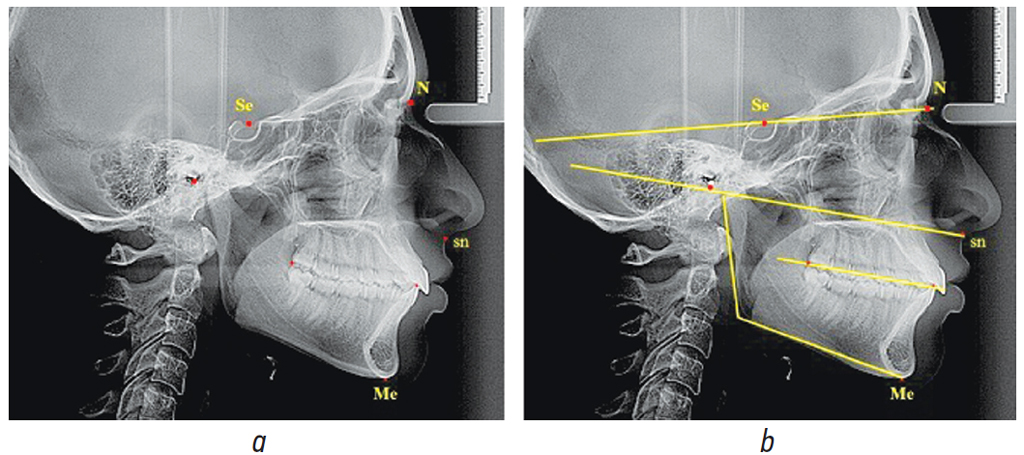

Из большого количества костных и кожных ориентиров, используемых в ортодонтии, нами были выбраны плоскость основания черепа по Шварцу (N-Se), мандибулярная плоскость и касательная к ветви челюсти с образованием и анализом нижнечелюстного угла. Камперовскую горизонталь проводили от субназальной до трагиональной точки, которая на телерентгенограмме соответствовала расположению нижнего края наружного слухового прохода. Окклюзионная линия соединяла контактную точку антагонирующих медиальных резцов с дистальной окклюзионной точкой последних моляров (рис. 1).

Рис. 1. Особенности анализа с расположением точек (а) и линий (b) для построения окклюзионной плоскости

Fig. 1. Analysis of the arrangement of points (a) and lines (b) for the construction of an occlusal plane